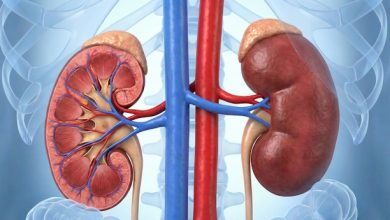

Ricerca e Clinica unite contro il carcinoma corticosurrenalico

L’AOU San Luigi Gonzaga di Orbassano conferma il proprio ruolo di riferimento internazionale nella ricerca sul carcinoma corticosurrenalico (ACC), un…